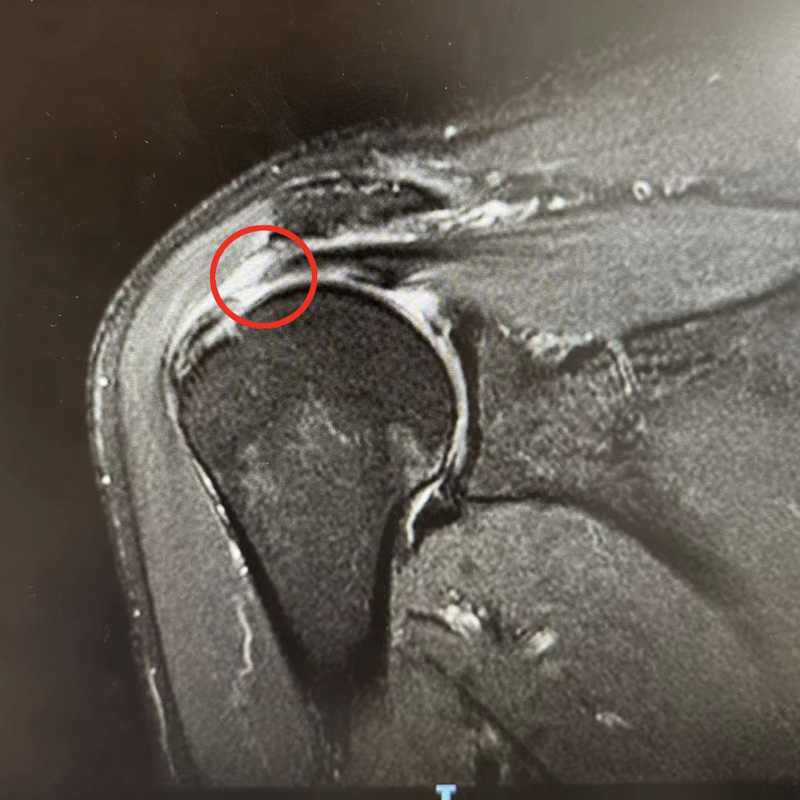

在郭老伯的比劃和親屬的手語翻譯下,運動醫學科副主任韋釗嵐慢慢了解了患者的病情,初步判定為肩袖損傷。此后的磁共振檢查也驗證了她的判斷,老人的肩袖損傷已達到十分嚴重的程度。

對于肩袖損傷,韋釗嵐醫生建議盡早治療。輕微的肩袖損傷,通過正規的保守治療能獲得較好療效,保守治療無效的,應盡早行手術治療。針對郭老伯的情況,運動醫學科團隊在關節鏡下對撕裂的岡上肌腱進行復位縫合固定,手術非常成功。